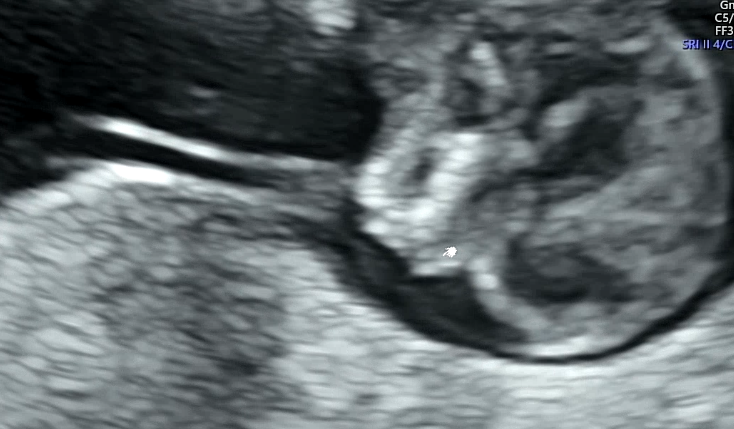

배 초음파를 하는데 태아가 꿈틀꿈틀 열심히도 움직였다. 백숙같은 몸매를 뽐내는 딱붕스

1차 기형아 검사의 포인트!

목투명대의 두께와 콧대의 유무이다.

태아가 너무 움직여서 심장소리와 목 투명대 길이를 재는데 애를 먹었다. 초음파를 보면서 귀엽다는 생각이 드는 나는 엄마가 되어가는 건가...!

목 투명대는 1.46mm가 나와서 정상이라고 하셨다. 1~3mm 사이면 정상 범위이고 3mm이상부터는 다운증후군 고위험군으로 판단된다. 그런데 2.5mm 대 정도도 걱정스러운 정도라서 좀 더 정확한 검사인 니프티 검사를 해보자고 하기도 한다.

콧대가 없으면 안면장애나 다운증후군이 의심되는데 콧대도 발견되었다!